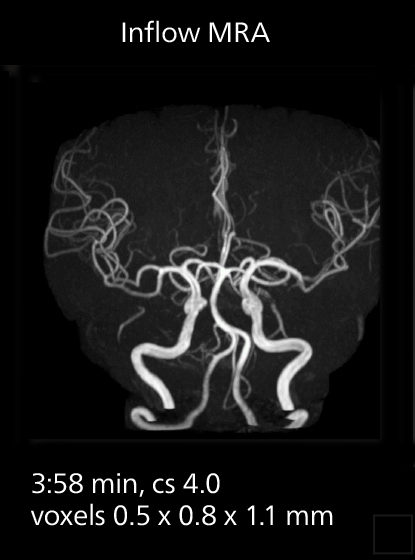

MRI of prostate

Examples of prostate imaging showing faster scan times and improved resolution illustrate the power of SmartPath to Elition X in this case of prostate cancer with PI-RADS score 4.

The high performance of the Vega HP gradients is particularly impressive in DWI. “The Vega HP gradients enable us to scan faster and use b-values as high as 2000, for example in prostate DWI and in DWIBS, which provides image quality that is remarkably improved over the previous system and we are able to more easily see lesions.”